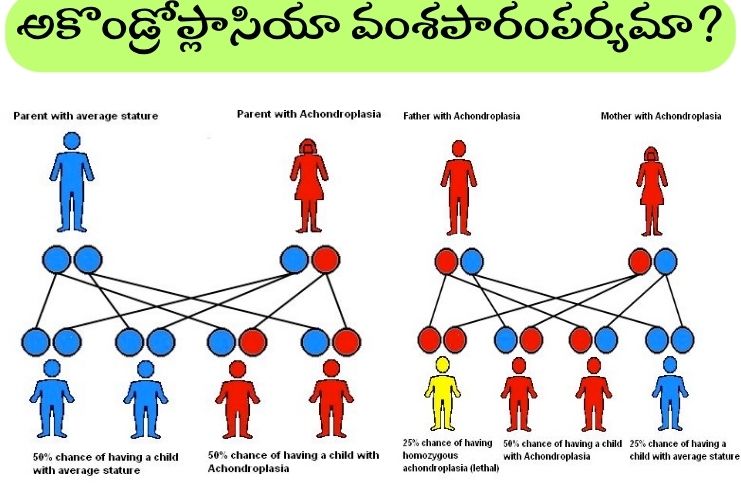

అకొండ్రోప్లాసియా వంశపారంపర్యంగా వస్తుందా? Is achondroplasia hereditary?

అకొండ్రోప్లాసియా యొక్క చాలా కేసులు వంశపారంపర్యంగా రావు. అకొండ్రోప్లాసియా ఎవరికైనా రావచ్చు. అకొండ్రోప్లాసియా ఉన్న వ్యక్తులలో సుమారు 80 శాతం మంది తల్లిదండ్రులు సాధారణ ఎత్తు ఉన్నవారై ఉంటారు. వారు ఒక కొత్త జన్యు మార్పుతో (డి నోవో మ్యుటేషన్) జన్మిస్తారు. ఈ తల్లిదండ్రులకు అకొండ్రోప్లాసియాతో మరో బిడ్డ పుట్టడం చాలా అరుదు. ఒక బిడ్డ అకొండ్రోప్లాసియాతో జన్మించడానికి తల్లిదండ్రులలో ఒకరు జన్యువును అందించినట్లయితే చాలు (ఆటోసోమల్ డామినెంట్). అకొండ్రోప్లాసియా ఉన్న వ్యక్తికి మరియు అకొండ్రోప్లాసియా లేని భాగస్వామికి ఈ రుగ్మతతో బిడ్డ పుట్టడానికి 50 శాతం అవకాశం ఉంది. తల్లిదండ్రులిద్దరికీ అకొండ్రోప్లాసియా ఉంటే, బిడ్డ హోమోజైగస్ అకొండ్రోప్లాసియాతో జన్మించడానికి 25 శాతం అవకాశం ఉంది. ఇది మృతశిశు జననానికి లేదా పుట్టిన కొద్దిసేపటికే మరణానికి దారితీస్తుంది.